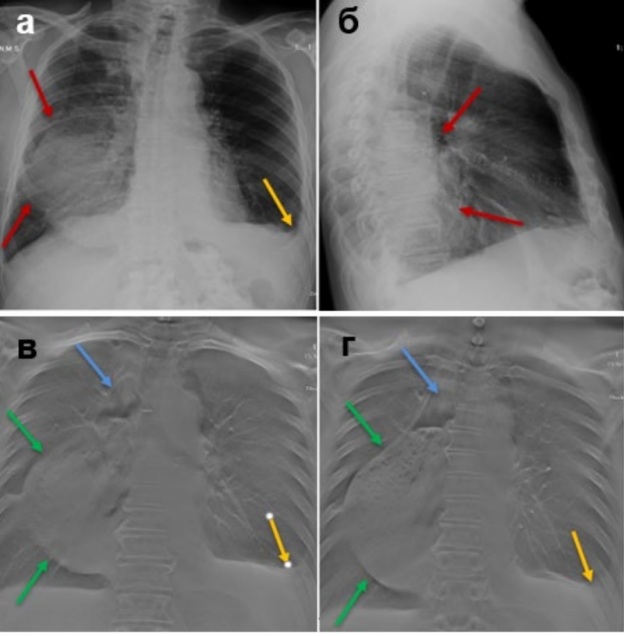

Расширенный желудочный стебель, гидроторакс слева: а – цифровая рентгенограмма ОГК в прямой проекции; б – цифровая рентгенограмма ОГК в правой боковой проекции; в, г – ТС ОГК.

На рисунке состояние после лапароскопии, торакотомии, расширенной субтотальной резекции пищевода с одномоментной пластикой широким желудочным стеблем и анастомозом в плевральной полости. На рентгенограмме грудной полости в нижней доле правого лёгкого определяется фокус неоднородного уплотнения лёгочной паренхимы (красные стрелки) – воспалительные изменения? желудочный стебель? В левой плевральной полости гидроторакс (жёлтая стрелка). При ТС – в правом гемитораксе определяется расширенный желудочный стебель – гастростаз (зелёные стрелки) – с неоднородным содержимым, наличием в нем газа (синие стрелки). Гидроторакс слева (жёлтые стрелки).